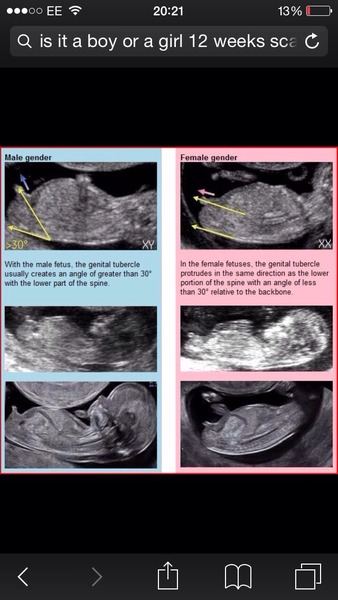

hayley that's the nub theory mine was exactly like the girl's one, just got to make sure your baby's nub is clear on the 12 weeks scan! :)